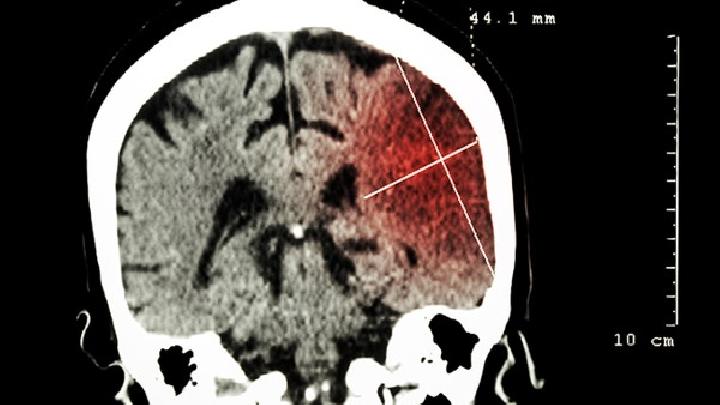

硬脑膜动静脉畸形症状

硬脑膜动静脉畸形治疗

硬脑膜动静脉畸形病因 硬脑膜动静脉畸形饮食